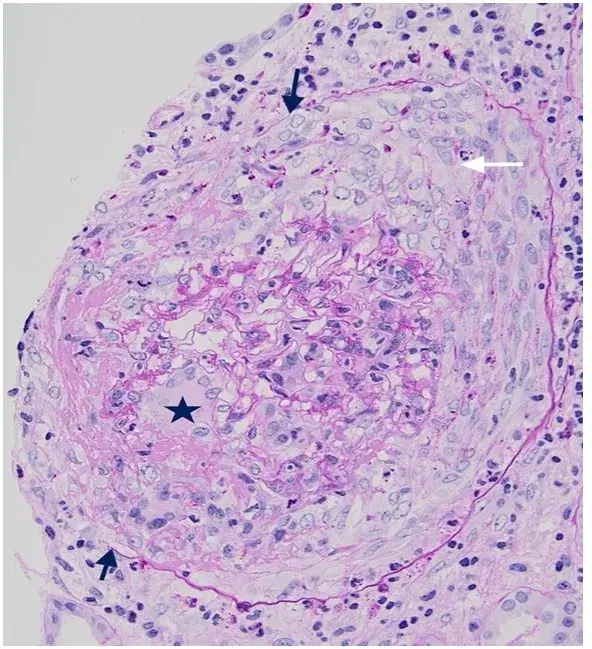

IRA, fadiga e sedimento urinário ativo